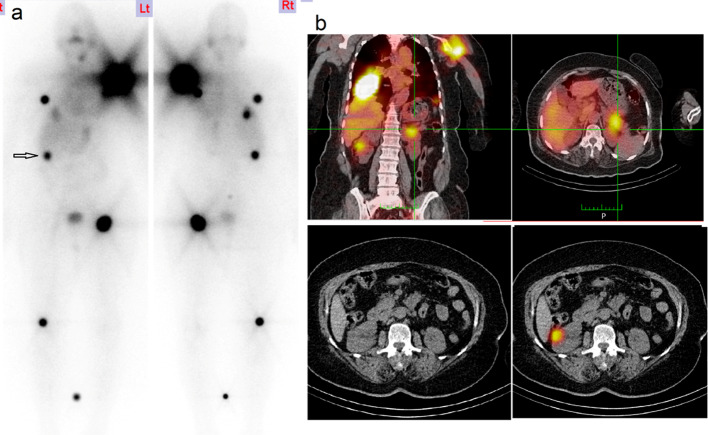

Only 58 cases of muscular metastasis from DTC have been reported, from 1907 to 2017. The most frequent muscles involved are the gluteus muscles. The majority of muscular metastases are correlated with worse survival (Tunio et al. 2013). In our series we have only one case of skeletal muscle metastases to temporalis and pterygoid muscles, the patient is female with FTC and she also had lung metastases, she received RAIT with progressive disease till now.18F FDG-PET /CT was done for confirmation Fig. 4.

Fig. 4.

a Post-therapy WBI scan showed uptake in left submandibular area misinterpreted as salivary gland activity, b follow-up post-therapy WBI scan revealed disease progression with increased uptake in submandibular region and increase in number and intensity of pulmonary lesions, c SPECT/CT images show iodine avid pterygoid muscles metastasis. d Whole body18F FDG-PET/CT coronal images show intense FDG uptake by left temporalis and pterygoid muscles indicating muscle metastases, e trans-axial images show increased FDG uptake by left temporalis muscle and f trans-axial images show increased FDG uptake by left pterygoid muscles